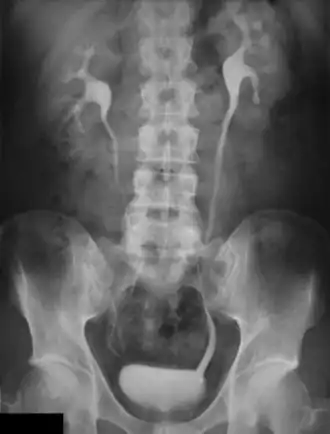

Urographie intraveineuse

L'urographie intraveineuse (UIV) est une technique d'examen radiologique qui permet d'explorer la morphologie du rein et la fonction rénale.